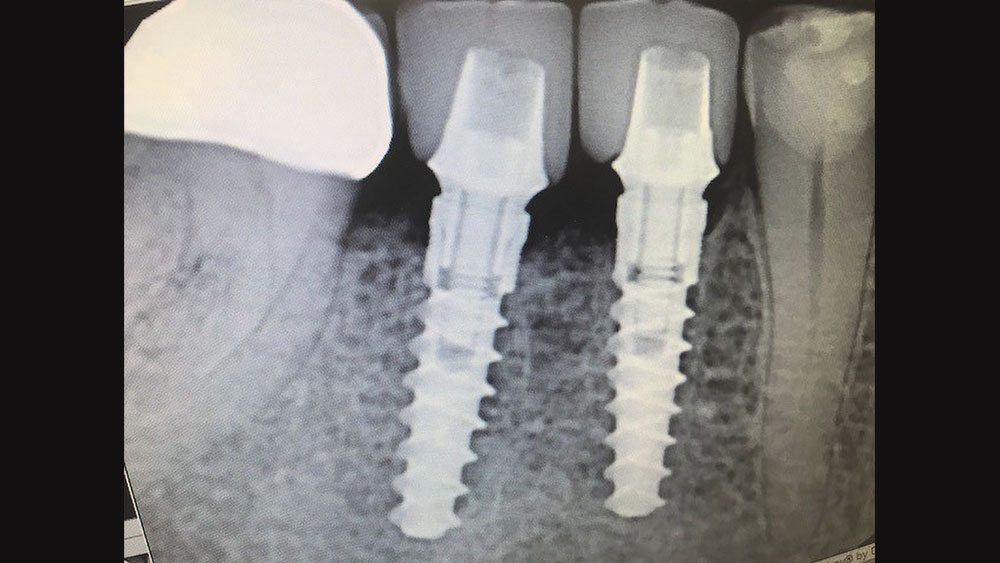

So that first experience was great, but the case I want to share is an interesting two-implant case I recently did to replace a single molar. The tooth could have been restored with a root canal, post and core, and crown, but implant treatment offered a better long-term prognosis and was the patient’s preference after learning of her options. We went with two 3.5 mm x 11.5 mm Hahn implants because the buccal-lingual bone width was too narrow to accommodate a larger implant and placing one implant of that size would have made the crown look like a lollipop. The biomechanics wouldn’t have been great either, so we went with two medium-sized premolars, which also resulted in better hygiene. I extracted the tooth, grafted the socket with Newport Biologics™ Mineralized Cortico/Cancellous Allograft Blend (Glidewell Direct), and placed the implants four months later.

CM: Did the surgical procedure go as you expected?

JG: The surgical procedure went very smoothly, like clockwork. There were no surprises, and the implants threaded into place very nicely. One of the things I like about the Hahn system is that the osteotomy drills account for the full body of the implant and create the precise amount of space you need. Other implant systems force you to jam the implant into virgin bone because the rounded corners of the implant are not accounted for in the shaping drill. And because they’re not self-tapping like the Hahn implant, this complicates things a bit. The Hahn implant system is very streamlined and makes for a more accurate fit between the osteotomy drills and the implant, using a very straightforward drilling sequence. You pick up on that within the first 10 minutes of looking at the surgical kit, which is very well thought out.